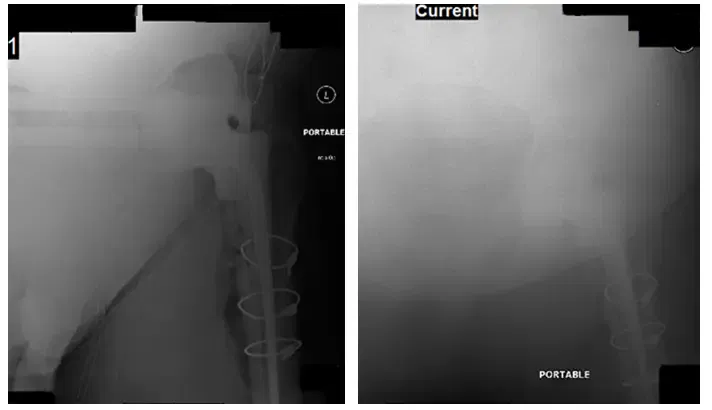

Le patient a fait un suivi 6 semaines après sa chirurgie de mise en place d’espaceurs et a apporté de nouvelles radiographies à examiner. À ce stade, après l’opération, la cicatrice du patient avait bien guéri et il avait une amplitude de mouvement modérément restreinte. On a conseillé au patient d’obtenir une aspiration de la hanche gauche et de suivre les résultats. On lui a également demandé de continuer à prendre des antibiotiques par ID et d’arrêter 2 semaines avant l’aspiration.

Le patient a fait un suivi environ 4 semaines après le retrait de l’espaceur et la révision de la THA gauche avec de nouvelles radiographies à examiner. Le patient présentait une restriction modérée de son amplitude de mouvement, une diminution de sa force et une atrophie. On lui a conseillé de continuer à prendre de l’aspirine 325 mg deux fois par jour, de la vitamine D3 5 000 UI par jour, et de suivre dans 6 semaines avec de nouvelles radiographies pour surveiller la progression postopératoire.